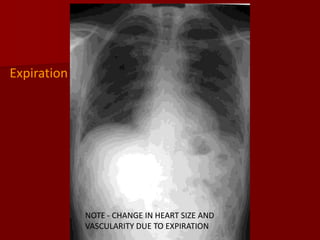

Inspiration:

The volume of air in the hemithorax will affect the

configuration of the heart in relation to cardiac size.

The vascular pattern in the lung fields will be

accentuated with a shallow inspiration.

The level of inspiration can be estimated by

counting ribs.

Visualization of nine posterior ribs, or seven

anterior ribs on an upright PA radiograph projecting

above the diaphragm would indicate a satisfactory

inspiration

Expiration

NOTE - CHANGE IN HEART SIZE AND

VASCULARITY DUE TO EXPIRATION